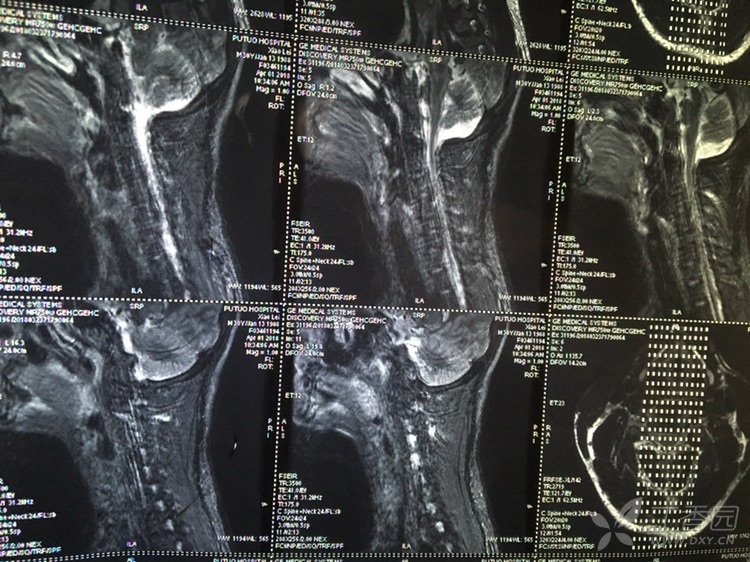

Feb 26, 21 · 颈椎压迫神经的症状分为压迫神经根和颈髓两方面。 颈椎压迫神经根的症状有:1、疼痛,一般表现为自颈部向上肢的放射性疼痛;2、感觉障碍,受到压迫神经根在上肢的支配区出现麻木、痛觉过敏、感觉减退等症状;3、肌力改变,早期肌张力亢进,晚期肌张力减弱,肌肉出现萎缩。Nov 08, 11 · 颈椎病吃药只是缓解作用,要除根的话建议您还是接受正规的治疗,最好是保守治疗,您与眩晕的情况的话应该属于脊髓型的,最好不要再耽误了,我们是通过中医手法复位正骨后(正骨12周,每隔一天一次,30分钟每次)改变压迫神经的关节位置使其不再压迫Aug 23, 19 · 虽然说确实有压迫神经的可能,但依然只是猜测,目前已有的检查并不能确诊! 患者需要做一个颈部核磁,这个检查是很有必要的,不光是确诊,更是未来治疗的依据,我们需要通过核磁更为详细的了解患者病情,病变位置、神经压迫程度进行综合考虑,对于此类患者来说,治疗方式有很多,作

May 18, 12 · 全部症状:手指没力肌肉萎缩 发病时间及原因:12年5月 治疗情况:先想咨询一下还没治有后遗症吗?,Apr 12, 17 · 颈椎病症状主要是由于神经受压引起的,那么治疗关键就在于解除对神经的压迫。 开刀手术是其中的一种的方法但是该病属于退行性疾病,一般情况下建议先配合保守治疗。Sep 26, 18 · 由于颈椎疾病病变导致的压迫神经,从而引发的神经激惹和神经损伤症状,应该属于神经根型颈椎病,应该针对这种神经损伤症状做系统的治疗。 首先,要做颈椎的电动牵引,配合微波理疗、活血化瘀药物治疗,并且可以使用甘露醇脱水治疗,同时可以口服甲钴胺片剂做神经营养治疗。

May 22, 10 · 颈椎开刀后导致神经压迫使手脚不灵活78年了 有什么办法可以治疗吗 急急,由于开刀的费用是非常昂贵的和可能出现的后遗症。所以,没有去开刀。 再一次偶然的机会女儿通过朋友的介绍,尝试了这"冷敷贴",结果用不到两个疗程就解决这老人家90%的困扰。 适合用于: 肩膀颈椎,腰部,手脚酸麻胀痛绷紧! 欢迎询问: 微信号tuckkhorFeb 02, 21 · 颈椎病的治疗以非手术治疗为主,如针灸、推拿、针刀、松解、药物治疗等,其中最常用的是药物治疗,包括膏药贴、口服药物等。 颈椎椎间盘突出可以压迫神经根,引起一系列颈丛、臂丛的症状,这类患者治疗时可以选用射频、臭氧、等离子方法治疗。 症状严重的颈椎病患者,如椎管狭窄非